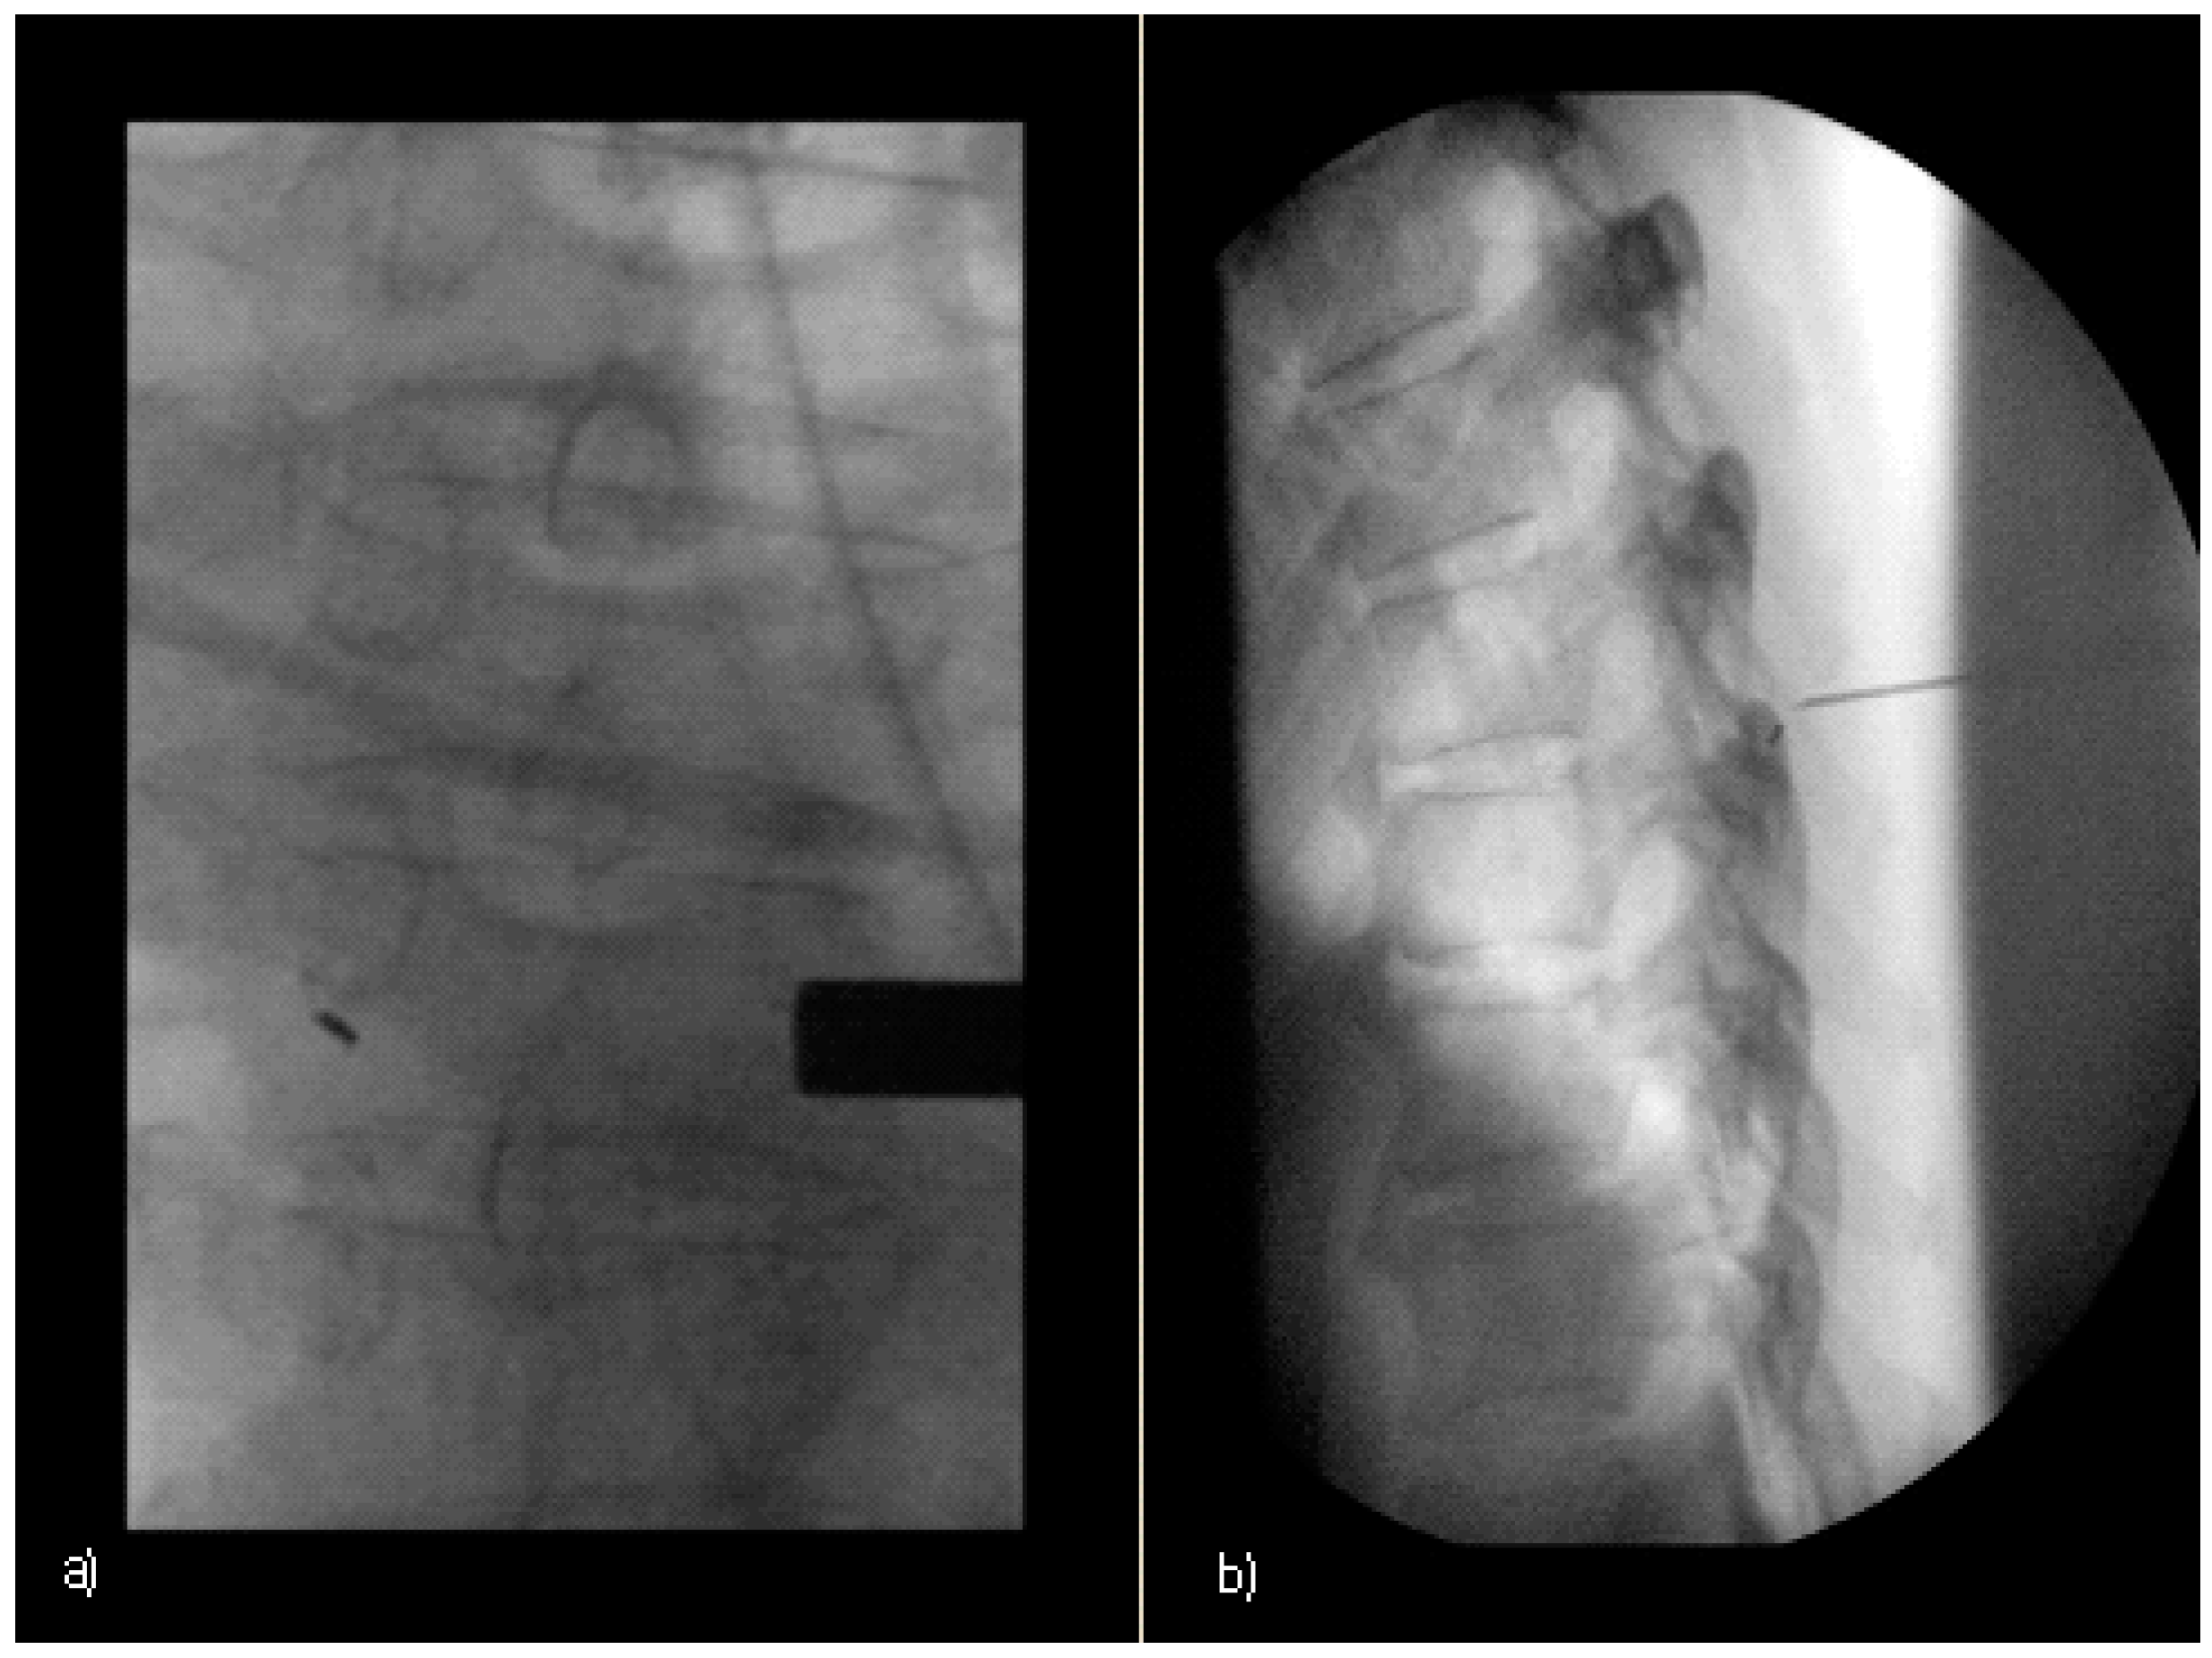

In the operating room (OR), the patient was placed in a stable prone position under general anesthesia. The surgical area was roughly defined using standard externally palpable anatomical landmarks, with the 1–2 mm skin incision made a maximum of 48 h prior to gold marking still visible in all patients. After extensive skin disinfection and sterile draping, the exact target level was verified by a single-shot C-arm image. Figure 2a shows the identification of the clearly visible preoperative gold marker.

A needle was then inserted percutaneously close to the contralateral lamina of the marked vertebral body. The needle serves as a guide and enables reliable preparation of the target plane. In case of uncertainties, the correspondence between the localization of the gold marker localization and the needle tip placement could be verified by means of an additional lateral image (Figure 2b).

Gold marker localization was generally performed using only one single shot image in the anterior–posterior orientation and additional lateral orientation as required by the operating surgeon.

The average CT-intervention time between the planning scout and the final CT control scan was 14.3 min. In all cases, the marker could be detected easily during surgery by fluoroscopy without the necessity of fluoroscopic visualization of additional anatomical landmarks (Figure 2).

Figure 2. Intraoperative gold marker identification with fluoroscopy: (a) 68-year-old patient (Table 1, patient number 10) anterior–posterior view (b) 56-year-old patient (Table 1, patient number 6) additional lateral view with a additional guiding needle.